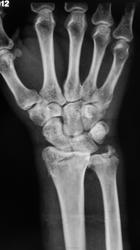

Травма. Пациент направлен на рентгенографию лучезапястного сустава.

перелом луча с отрывом шиловидного отростка. Вывих в лучезапястном суставе. Видимо упал с лестницы или неудачное голосование?

Истинный тыльный вывих кисти. Внутрисуставной оскольчатый перелом лучевой в типичном месте, перелом шиловидного отростка локтевой со смещением. А контроль после репозиции будет?